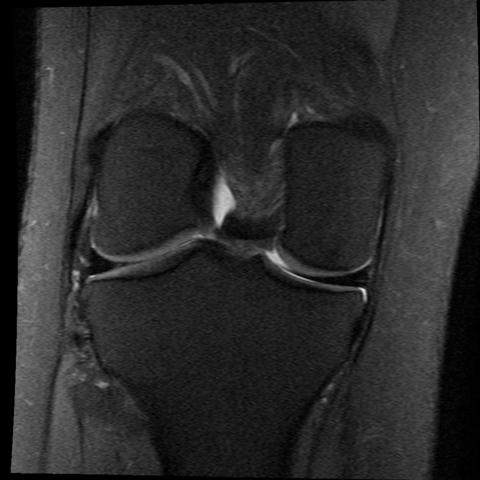

Gesundes Kniegelenk Mrt

Mrt Des Kniegelenkes Anatomie

Das Knie Mrt Anatomieatlas In Medizinischer Bildgebung